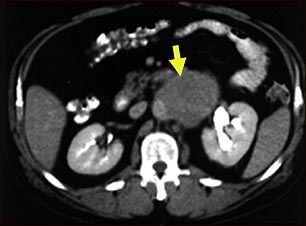

Tomografía computarizada de metástasis a los ganglios linfáticos

TC del abdomen medio mostrando un gran tumor debido a metástasis (cáncer diseminado) en los ganglios linfáticos abdominales.